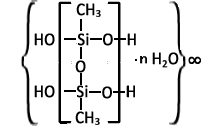

Structure

Enterosgel (PMSPH) or methylsilicic acid hydrogel is a polymeric gelatinous organosilicon compound. The gel is dispersed in water to a particle size of no more than 300 microns. The preparation is a suspension which is taken orally

Microstructure

Electron microscopic studies have shown that its gel-forming matrix has a globular structure and consists of an ensemble of fused globules. These globules, bound together by siloxane bonds, form pores. The pores are the spaces between the globules. They are filled with water. Pore size is restricted.[6]: 38 The presence of methyl groups on the surface ensures its hydrophobic properties.[6]: 27 Enterosgel particles (PMSPH) tend to form a continuous network in a suspension to reduce the interaction of hydrophobic SiCH3 with water. These particles can be viewed as two-dimensional sheets rather than three-dimensional solid particles. Aqueous suspensions of polymethylsiloxane polyhydrate are characterized by high viscosity.[7]